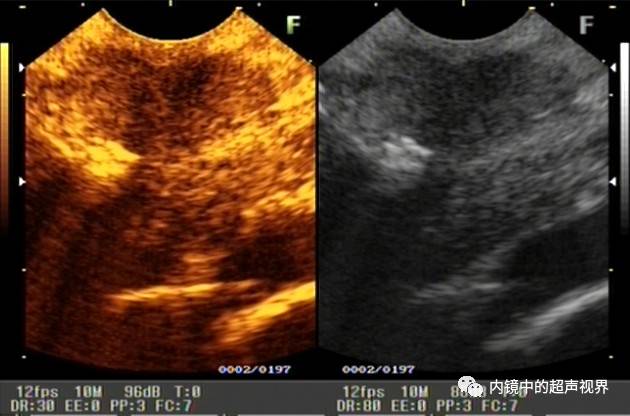

再来一张间质瘤的图片,也是DR30和80的对比。

有没人觉得,这个间质瘤的图片跟前面两个病灶不太一样,似乎感觉高DR模式看起来更舒服,那是因为,间质瘤为低回声,它周围的软组织为高回声,本身就能形成良好的对比,无需降低DR,而高DR模式更显细腻。

间质瘤